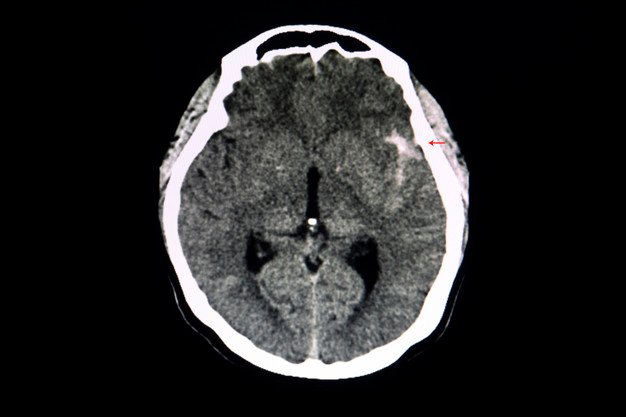

Você sabia que o Acidente Vascular Cerebral (também conhecido com AVC ou derrame) é uma das doenças que mais mata no nos países em desenvolvimento